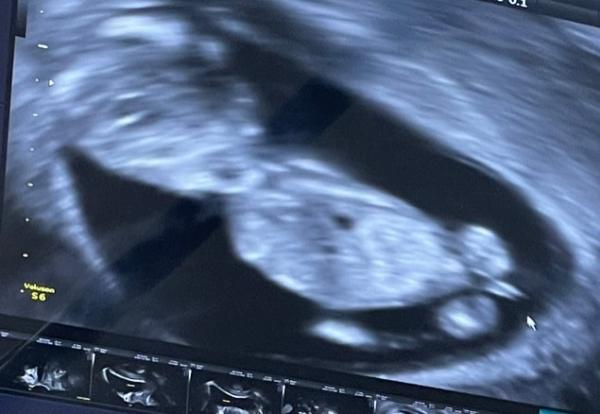

Hallo ihr Lieben, mein Arzt meinte das da sieht „eher wie ein Penis aus“ aber ich soll trotzdem „nicht so viel drauf geben“ Was meint ihr!? Junge oder Mädchen? LG

Hey, für mich könnte es bei dem Winkel der Beine ein Fuß sein Weiß ja nicht wie groß das geschlechtsteil in dieser Woche zum Rest des Körpers ist, aber bei der Geburt sind die ja minimal Bei uns lag er/sie (divers kommt später) auch super, aber unsere Ärztin meinte da braucht man noch nicht schätzen, dass wäre meistens ein Ratespiel

Hey. Ich denke auch es ist ggf ein anderes Körperteil. Scheint mir proportional etwas zu groß für einen Penis.